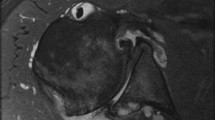

Standardized preoperative and postoperative radiographs included AP and axillary lateral views [17,18,19, 48]. Adequate observation of the spinoglenoid notch confirmed proper orientation of the axillary view [19, 29]. Because of the demonstrated utility and reproducibility of this method and to avoid unnecessary cost and radiation exposure, preoperative and postoperative CT scans were not obtained [29]. Acceptability of the images and radiographic assessments of glenoid version, glenoid type, postoperative glenoid lucencies, and glenoid decentering were performed by two board-eligible and one fellowship trained shoulder surgeons who were not involved in the care of these patients (BCS, JSS, JEH), who were blinded to the clinical outcome, and who were experienced in making these measurements [19] (Fig. 6). Measurement of preoperative humeral head decentering also was done (Fig. 7). The immediate postoperative version of the glenoid component was measured as the angle between the scapular body plane and a line through the metal marker of the central peg (Fig. 8). Posterior humeral head decentering was measured on the radiograph obtained at the 2-year followup as the percent of the humeral head posterior to a line perpendicular to the midpoint of the glenoid face (Fig. 9) [19]. We use the term ‘decentering’ of the humeral head with respect to the glenoid fossa to avoid confusion with the term ‘subluxation’ which often is used to refer to the relationship of the humeral head to the plane of the scapula [45].

The radiographic measurement of preoperative glenoid version is shown. A line segment is drawn connecting the anterior (A) and posterior (C) edges of the glenoid. Line B-X is the perpendicular bisector of this line segment (the glenoid centerline). Line B-Y is drawn along the plane of the scapula. The angle between B-X and B-Y is the glenoid retroversion.

The radiographic measurement of preoperative posterior decentering is shown. It is expressed as the percent of the humeral head circle lying behind the glenoid centerline on the standardized axillary view taken with the arm in the functional position of elevation in the plane of the scapula. The humeral head circle is drawn with point Z marking the center of this circle. A line segment is drawn connecting the anterior (A) and posterior (C) edges of the glenoid. Line B-X is the perpendicular bisector of this line segment (the glenoid centerline). Line segment D-F marks the diameter of the humeral head circle drawn parallel to line segment A-C. Point E marks the intersection between D-F and B-X. The percentage of the humeral head circle lying behind the glenoid centerline is calculated as (E-Z)/(D-F) × 100%.

The radiographic measurement of postoperative glenoid component version is shown. A line segment is drawn connecting the anterior (A) and posterior (C) edges of the glenoid component with point B bisecting the line between A and C. Line B-X, the glenoid component centerline, is drawn along the metal marker in the central peg of the glenoid component (black arrow). Line B-Y is drawn along the plane of the scapular body. The angle between these two lines is glenoid component retroversion.

The radiographic measurement of postoperative posterior decentering is shown. It is expressed as the percent of the humeral head circle lying behind the centerline of the glenoid component on the standardized axillary view taken with the arm in the functional position of elevation in the plane of the scapula. The humeral head circle is drawn with point Z marking the center of this circle. Line B-X, the glenoid component centerline, is drawn along the metal marker in the central peg of the glenoid component (black arrow). Line segment D-F marks the diameter of the humeral head circle perpendicular to the glenoid centerline with point E marking the intersection between D-F and B-X. The percentage of the humeral head circle lying behind the glenoid centerline is calculated as (E-Z)/(D-F) x 100%. A centered humeral head with 0% posterior decentering is shown in this figure.